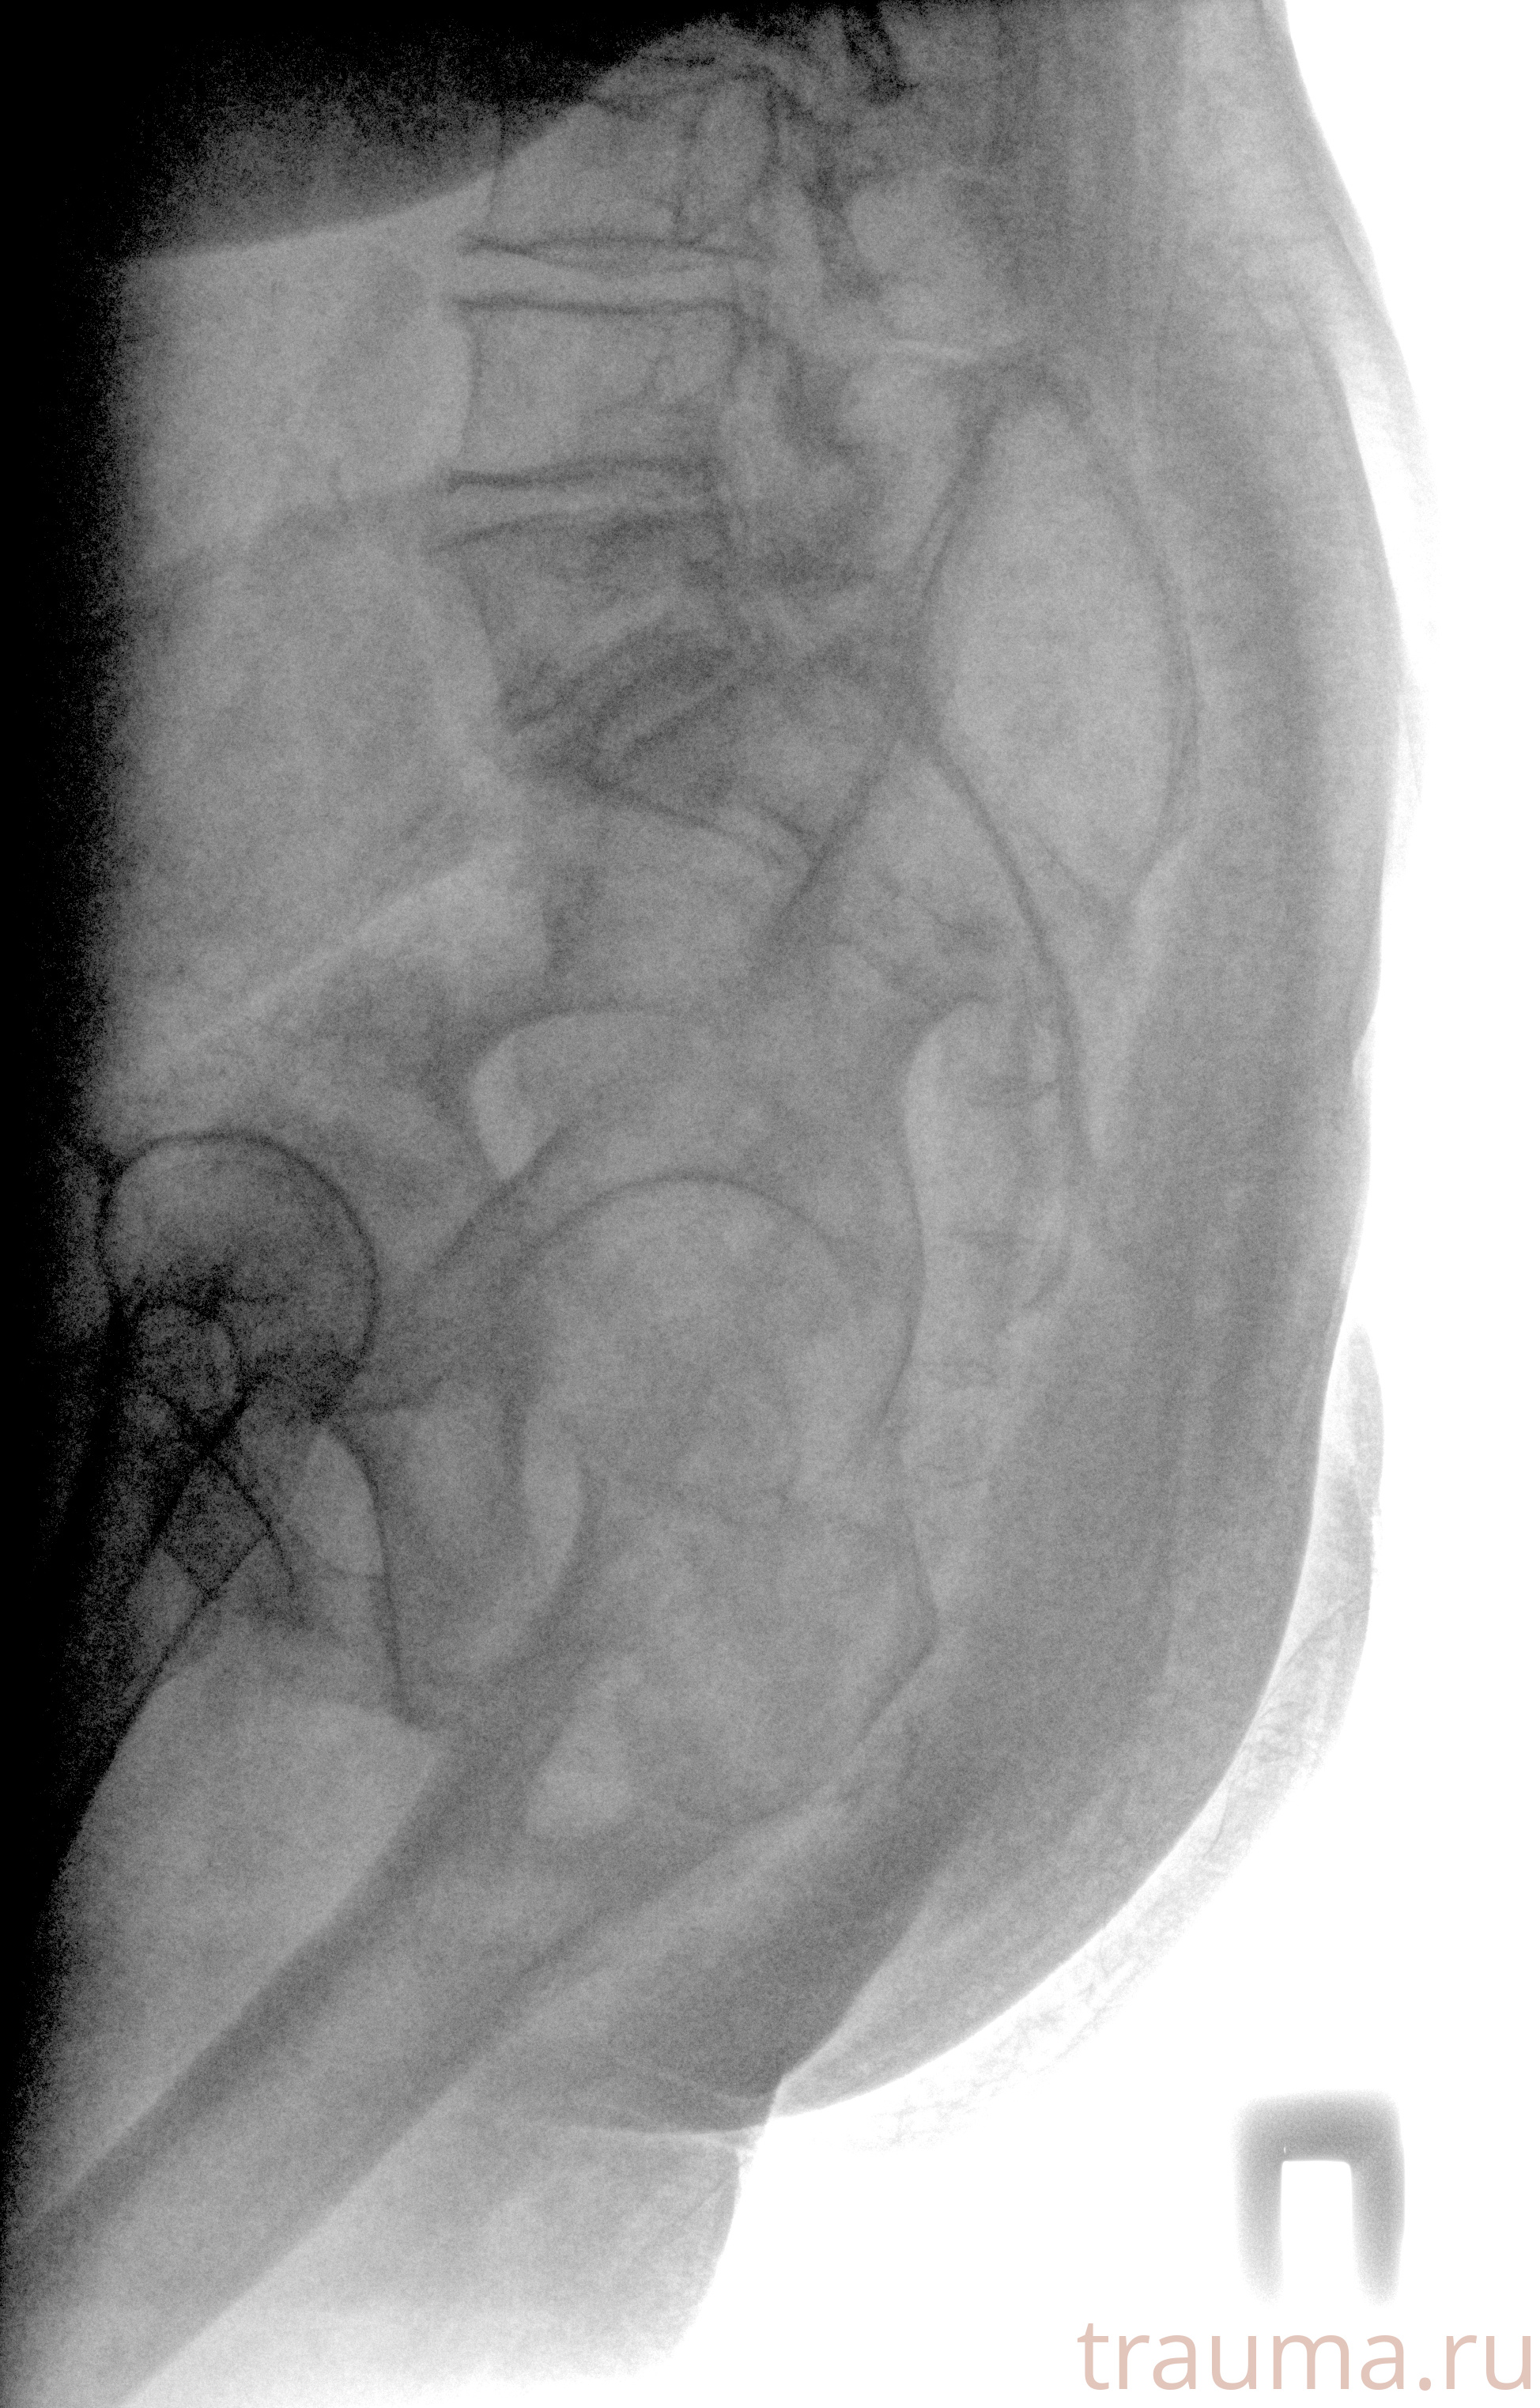

Рентген на дому: по вашему адресу приезжает врач-рентгенолог, травматолог-ортопед с мобильным рентгеновским аппаратом, проводит диагностику травмы или заболевания, делает необходимые рентгенограммы, дает рекомендации по дальнейшему лечению. Получить качественные снимки в домашних условиях возможно благодаря уникальной методике, разработанной МосРентген Центром для института  Склифосовского

при переломе шейки бедра и пневмонии от компании МосРентген Центр - партнера Института имени Склифосовского